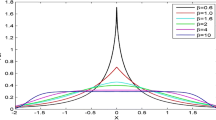

Active contour methods (ACM) are model-based approaches for image segmentation and were developed in the late 1980s. ACM can be divided into two classes: parametric active contour model and geometric active contour model. Geometric method is intrinsic model. Because of its completeness in mathematics, geometric active contour model overcomes many difficulties of the parametric active contour model. However, in medical images with heavy structural noise, the evolution of the geometric active contour will be seriously affected. To handle this problem, this paper proposed a multiscale geometric active contour model, based on the multiscale analysis method—bidimensional empirical mode decomposition. In the human kidney MR images, the proposed multiscale geometric active contour model successfully extracts the complex kidney contour.

Flandrin, P., Rilling, G.: Empirical mode decomposition as a filter bank. IEEE Signal Proc. Lett. 11(2), 112–114 (2004)